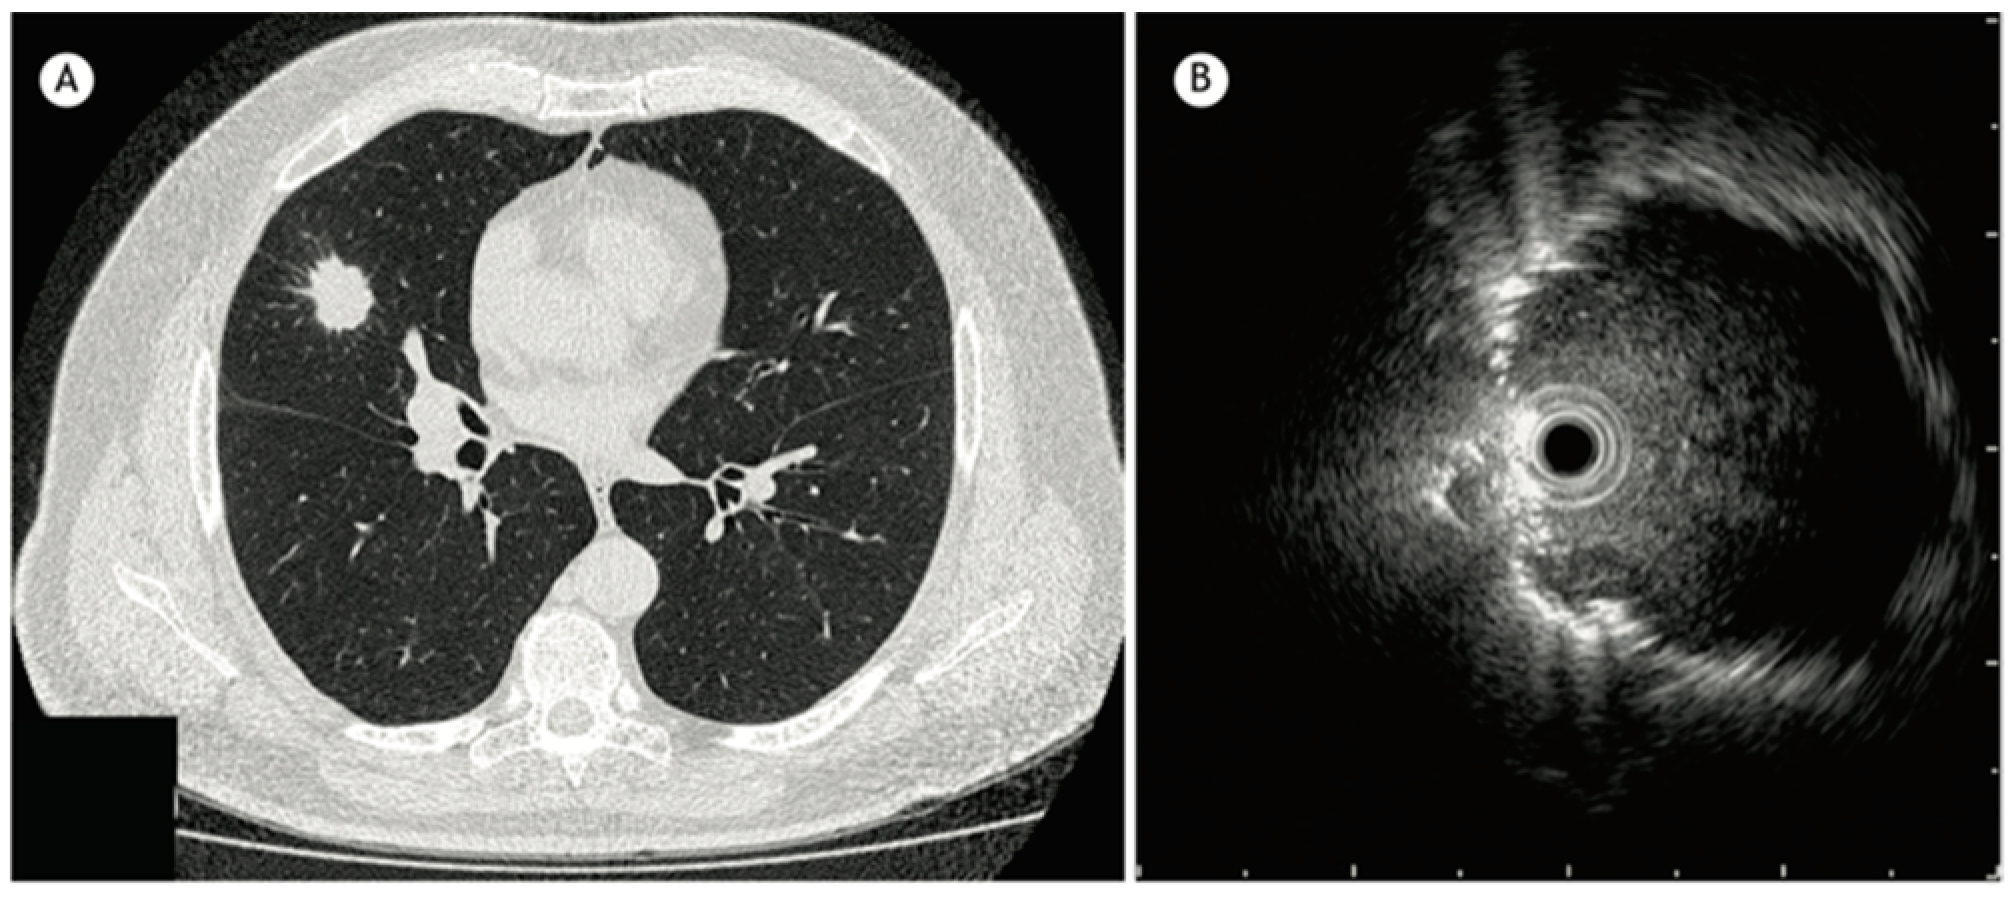

In addition to HRCT, there are several other imaging advancements very similar to the ones discussed in the lung cancer section that help in the diagnosis and monitoring of parenchymal lung diseases, including OCT, ultrasound, and PET. Earlier, we reviewed how OCT can be helpful for diagnosing lung nodules. Similarly, OCT offers minimally invasive high-resolution images for ILD diagnosis [20]. OCT has been shown to have sensitivity and specificity of 100% in detecting usual interstitial pneumonia patterns [21]. External validation and larger studies are required for clinical implementation. This could reduce reliance on surgical lung biopsy. Another form of imaging used includes ultrasound, which we have seen used for lung nodules as well. For parenchymal lung diseases, the pattern of abnormality is typically more diffuse. The radial ultrasound probe is inserted through a bronchoscope into the patient’s airways until it reaches the pleural surface. The probe is then slowly withdrawn from the pleura to the hilum, while examining the characteristics on the ultrasound image. This method helps determine a better location to biopsy. A dense sign correlates with a higher pathological confidence than a blizzard sign (Figure 3). Moreover, radial EBUS helps clinicians choose appropriate biopsy sites for cryobiopsy and identify blood vessels close to lesions, which should be avoided when a biopsy is performed. Minoru et al. demonstrated high-quality lung specimens with dense signs on radial EBUS while decreasing the bleeding risk [22]. Sarcoidosis is another common multisystemic disease characterized by the formation of non-caseating granulomas in various organ systems. Establishing the presence of inflammatory activity is crucial for diagnosis and the monitoring of treatment. One of the most common organs affected by sarcoidosis include the lungs. This condition affects the lungs in more than 90% of patients [23]. Sarcoidosis can affect the parenchyma, the mediastinal and hilar lymph nodes, or both. Increased FDG uptake in the pulmonary parenchyma is associated with inflammatory activity, presumably inflammatory cells, including activated macrophages, lymphocytes, and neutrophils, and, possibly, disease severity (Figure 4). One cannot solely rely on a PET scan for diagnosis and must use other forms of diagnosis, including history, physical examination, and serologic markers. It was found by Mostard et al. that 20% PET scans are positive without serological signs of inflammatory activity. PET can add value to the assessment of sarcoidosis and other inflammatory lung diseases in patients with symptoms despite the absence of serologic inflammatory markers [24]. Other patients do not exhibit parenchymal disease and just have mediastinal and hilar lymphadenopathy. In addition to PET scans, which can show hypermetabolic uptake in lymph nodes, ultrasound with linear EBUS can be used to examine the lymph node in real time and obtain tissue samples. Characteristics that can be examined include lymph node size, shape, margin, echogenicity, central hilar structure, and granular appearance (Figure 5). Furthermore, EBUS TBNA has shown a sensitivity of 89–100% and a specificity of 94–96% in diagnosing sarcoidosis [25]. This procedure and imaging technique can be used for diagnosing other thoracic diseases that infiltrate the mediastinal and hilar lymph nodes, such as infectious causes like TB or fungal infections, other inflammatory diseases like hypersensitivity pneumonitis and vasculitis, and malignant diseases.

Figure 4. PET image at the thoracic level showing diffuse bilateral parenchymal FDG uptake. Reproduced from Mostard et al., 2011 [24]. Reprinted from Respiratory Medicine 105, 1917–1924 (2011) with permission from Elsevier.